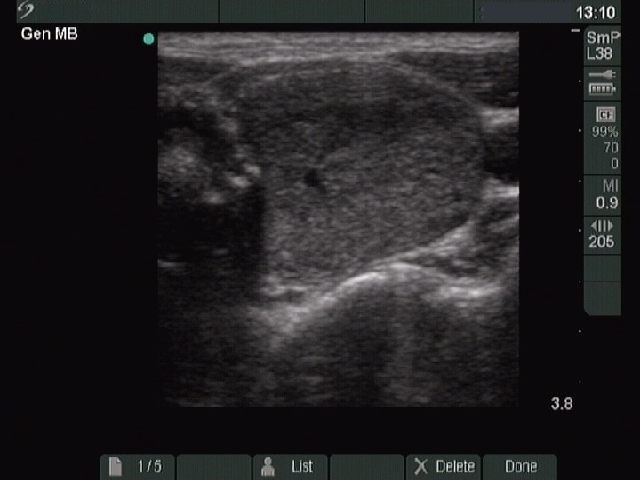

Ultrasonography: a solitary hypoechogenic nodule in the left lobe without a halo sign on gray scale mode. Doppler method disclosed perinodular vascularization.